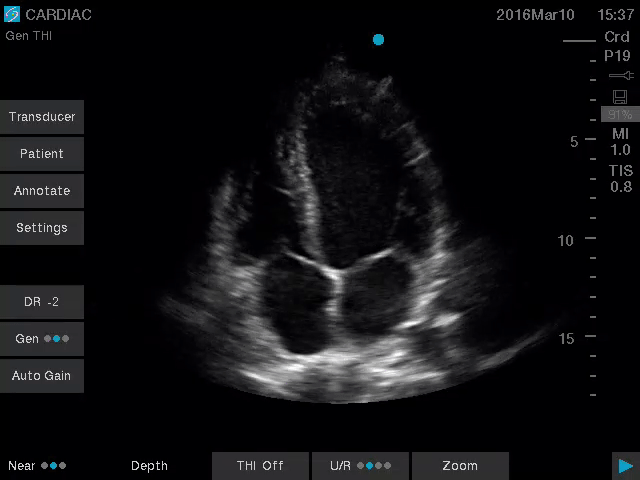

Vasküler Erişim için Sonosite SII-VA, hat yerleştirmeleri sırasında kullanım kolaylığı ve güvenilirliği nedeniyle klinisyenler için ideal bir araçtır. Basitleştirilmiş, dayanıklı ve uygun fiyatlı olan bu sistem, birincil bir amaç için yaratılmıştır: Ultrason rehberliğinin yardımıyla Merkezi hatlar, PICC’ler ve Periferik IV’ler gibi vasküler erişim prosedürlerinin başarı oranlarını iyileştirmenize yardımcı olmak.

Daha iyi görüş, daha derin anlayış. Sonosite, klinisyenlerin en zorlu ihtiyaçlarını karşılamak için yeni bir görüntü performansı standardını yeniden tanımlıyor.